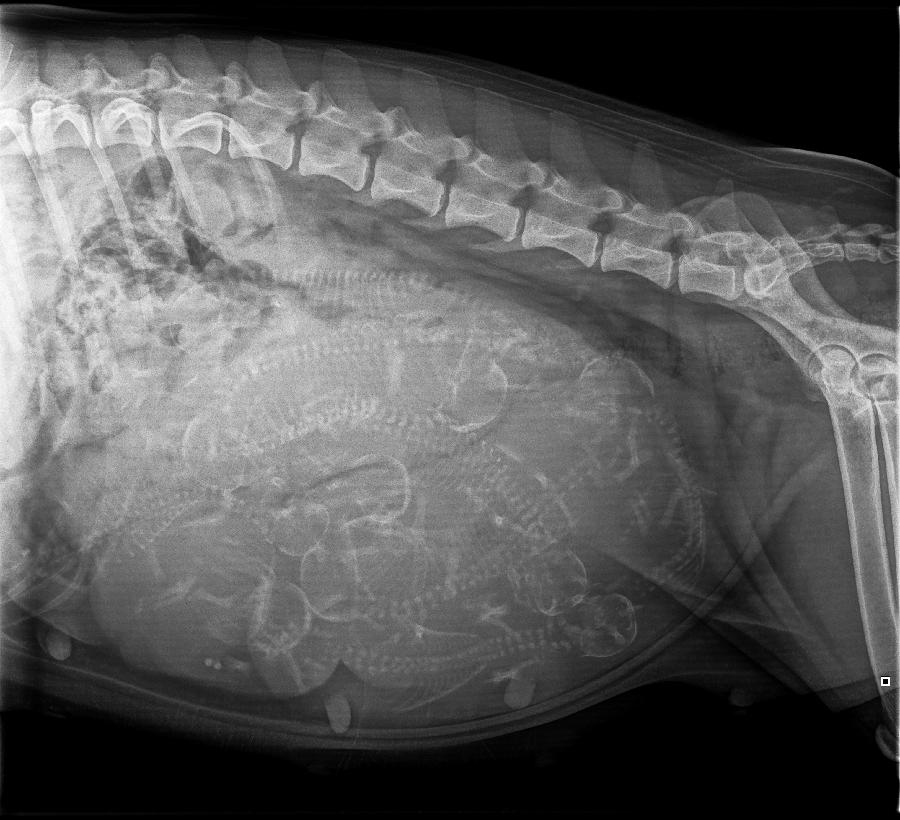

Op de eerste officiële lenteavond (zaterdag 21 maart) mochten we maar liefst tien kleine wonderen verwelkomen. Met vier lieve reutjes en zes stoere teefjes is het een gezellige boel in huis.